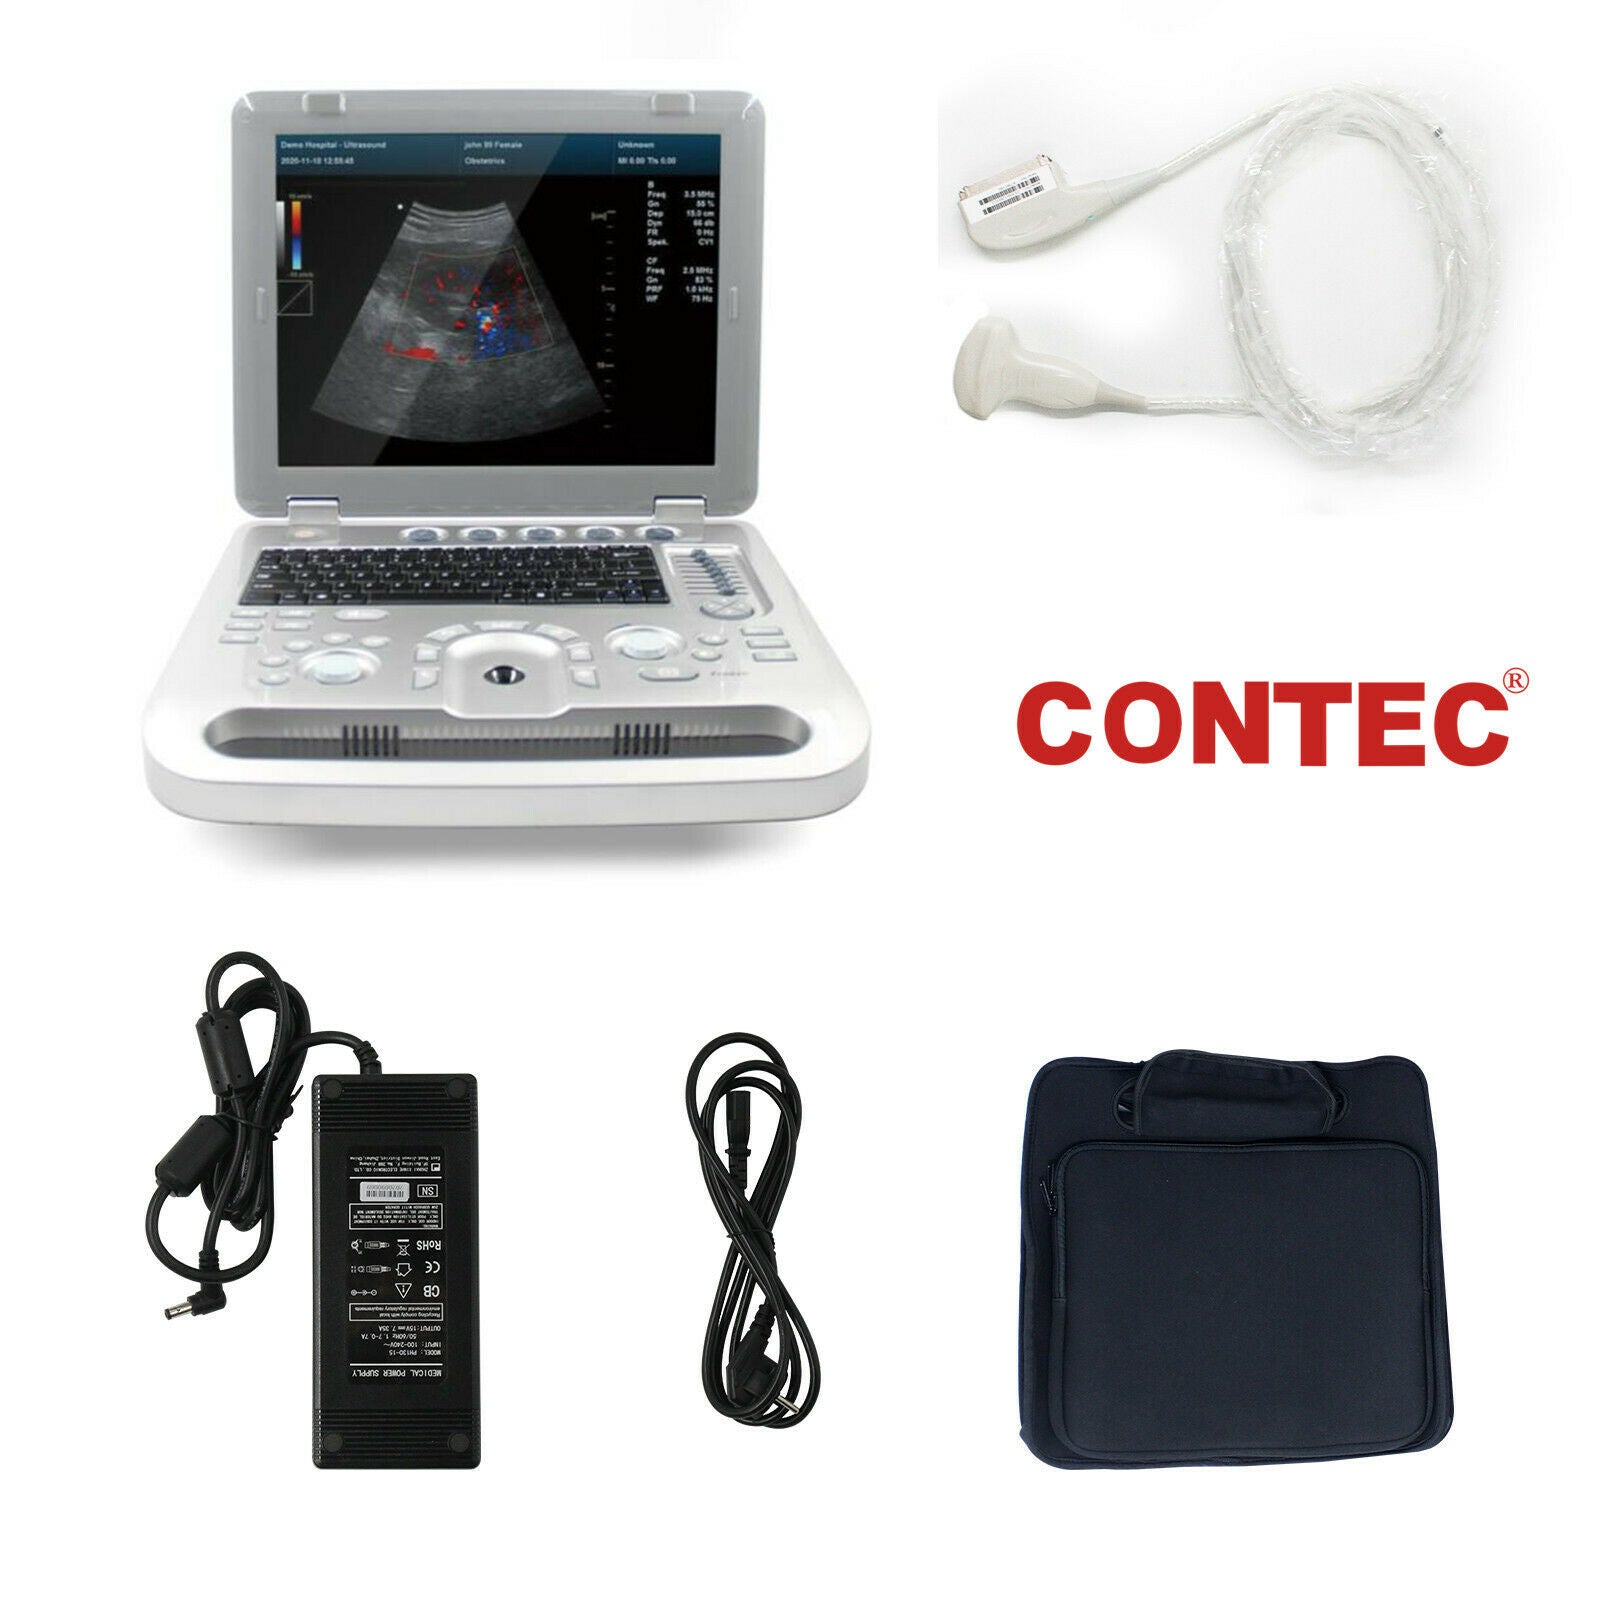

The Laptop Color Doppler Ultrasound is an innovative diagnostic machine designed for clear and precise imaging. It boasts advanced features, making it an indispensable tool for medical professionals. Whether you're in a hospital setting or a small clinic, this portable ultrasound scanner provides accurate diagnostics without compromising on quality.

One of the key features of the Laptop Color Doppler Ultrasound is its portability. This means you can easily transport it between examination rooms or even take it off-site when necessary. Despite its compact size, it offers robust capabilities that rival larger, stationary units. Medical professionals appreciate the balance of convenience and high performance it offers.

Additionally, the device includes Power Doppler functionality, which enhances the ability to detect blood flow and other internal processes. This technology provides more detailed imaging, allowing for better patient assessment and treatment planning. The Doppler ultrasound functionality ensures that even the smallest anomalies can be detected with clarity and precision.

The user interface of the Laptop Color Doppler Ultrasound is designed for ease of use. It features a high-resolution display, intuitive controls, and customizable settings. This makes it accessible for both new and experienced Sonographers. The device runs on powerful software that supports various diagnostic applications, ensuring versatility in its use. Therefore, it can be used for a wide range of procedures, from obstetric exams to cardiac assessments.

Battery life is another significant advantage. The Laptop Color Doppler Ultrasound comes with a long-lasting battery, ensuring that it can function effectively for hours. This is particularly useful in emergency situations or in settings where power supply is unreliable. The battery can be quickly recharged, minimizing downtime and ensuring the device is always ready for use.

Connectivity options are also impressive. The Laptop Color Doppler Ultrasound can easily connect to other devices and health information systems. This facilitates seamless data transfer and integration, enhancing workflow efficiency and patient record management. The ability to share diagnostic images and data quickly can significantly improve patient outcomes.

In conclusion, the Laptop Color Doppler Ultrasound Scanner is a state-of-the-art diagnostic tool that champions both portability and functionality. It stands out in the field for its advanced features like Power Doppler imaging, user-friendly interface, long battery life, and robust build. As a result, it is highly recommended for medical professionals who seek reliable, accurate, and efficient ultrasound solutions.